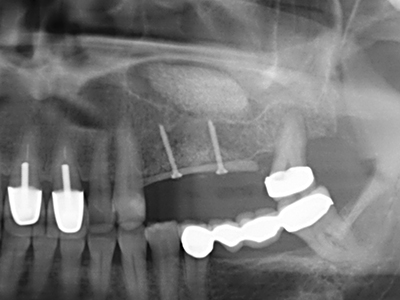

Indication: Bone splitting

Bone tissue is not simply a mineral structure but also contains a substantial proportion of collagen fibres. This means it not only has good compressive strength but also a degree of flexibility, which can be taken advantage of when performing bone augmentations. In the classical expansion procedure using bone splitting, the atrophied alveolar ridge is split longitudinally and carefully expanded after reaching an adequate osteotomy depth (Fig. 13-16), ideally without substantial removal of the periosteum (Brugnami, Caiazzo et al. 2014, Stricker, Fleiner et al. 2014). Screw and plate systems with increasing expansion distance have proven effective in separating the two bone lamellae while remaining below the fracture threshold. In general, residual bone widths of at least 3–4 mm are required (Chiapasco, Zaniboni et al. 2006) to guarantee adequate flexibility and sufficient bone coverage of the future implants. If necessary, a vertical relief osteotomy on one or both sides can improve flexibility. A combination with additional augmentation techniques, particularly on the buccal side, has been described as an alternative to the classical technique.

The splitting procedure is particularly atraumatic and there is no significant loss of dimension when using piezosaws, and there are no significant differences between implants in split jaws and implants in an alveolar ridge without a bone deficit (Chiapasco, Zaniboni et al. 2006, Danza, Guidi et al. 2009). However, sufficient continuous irrigation is essential, particularly with locally restricted and deep splitting to prevent thermal stress in the apical osteotomy regions.